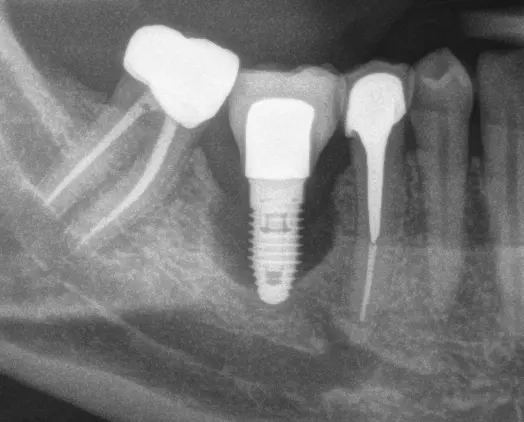

ZERAMEX XT Implant Placement by Dr. Shelby Nelson of Custom Periodontics & Implantology

Dr. Shelby Nelson of Custom Periodontics & Implantology shares her experience in placing her first ever Ceramic Dental Implant. Continue reading to know the reasons why she chose to move forward with ZERAMEX XT!